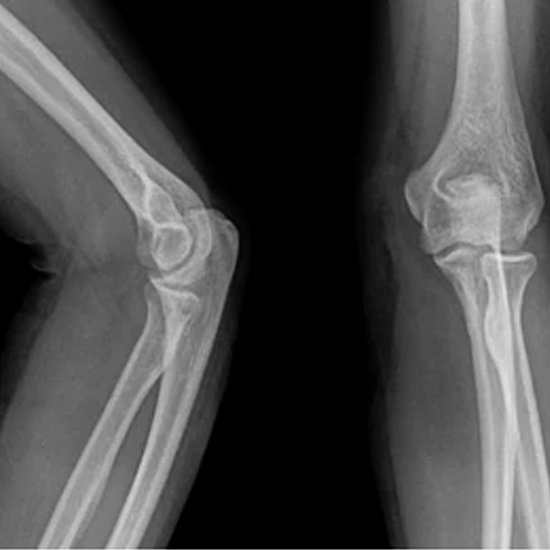

The bones of the upper arm, forearm, and elbow joint are all in the elbow area. In Anterior-Posterior (AP) projection, X-rays go from the front to the back of the patient. The side view is taken from the side of the patient. This checks for broken bones and dislocations near the elbow joint.